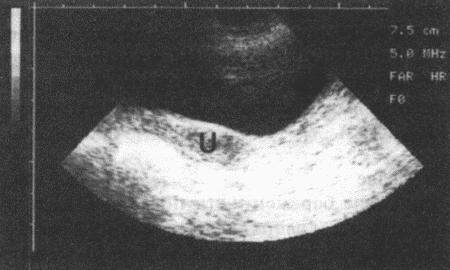

Фиг. 11.3.

Ультразвуковое изображение матки (U), расположенной дорсально от анэхогенного мочевого пузыря. Сука исследована в стоячем положении, датчик устанавливали на вентральную брюшную стенку. Датчик на 5 МГц, шкала в см